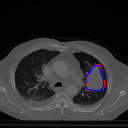

A qualitative analysis of our results reveals the strengths and weaknesses of our proposed model. In most cases, regardless of the size of the ground truth, our model predicts the tumor shapes very well. This is evident from Figure 4 where the ground truth and the prediction (by Deeply Supervised MultiResUNet) are shown in red and blue respectively. Although the tumors are in various arbitrary locations within the lung and appear in diverse sizes, the red and blue margins appear to coincide almost perfectly.

Figure 5 shows a comparison between predictions by the MultiResUNet model and Deeply supervised MultiResUNet model. It can be seen that the latter can delineate the tumor edges more accurately than the former. The ground truth (shown in red) and the prediction (shown in blue) have a more consistent alignment with each other in Deeply Supervised MultiResUNet’s prediction.